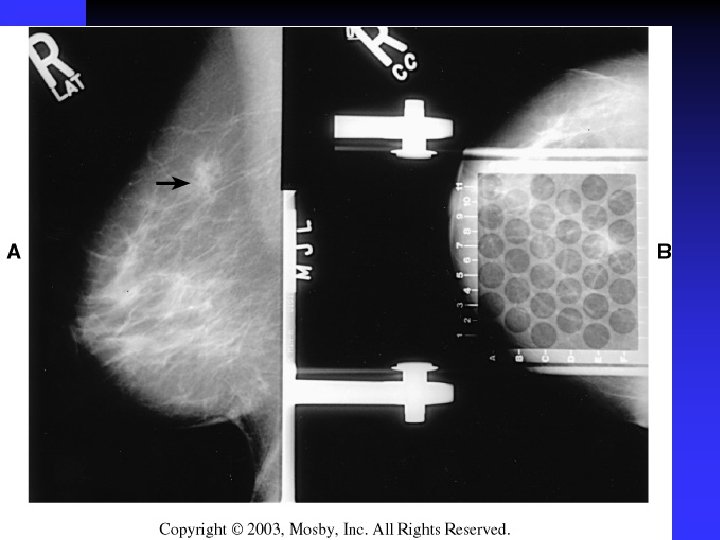

importance of high-quality mammograms is evident in the two images of the same breast